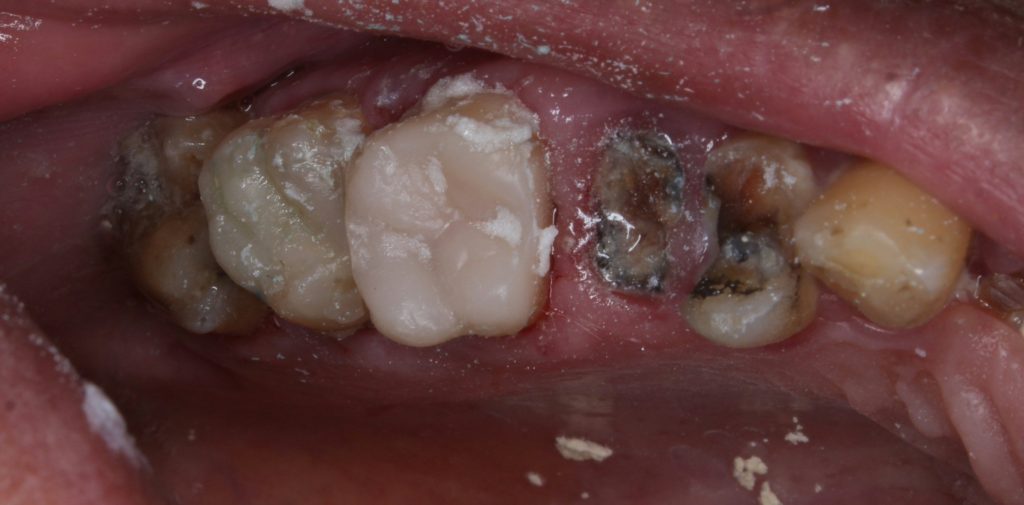

After local anesthesia and proper isolation with rubber dam, the old amalgam was carefully removed. Upon removal, deep margins were detected and all cavity walls were undermined, necessitating complete removal of unsupported enamel and defective dentin.

Caries excavation was performed until sound dentin was reached. Due to the depth of the cavity and the loss of wall support, gingival retraction was done to gain access and visibility to the deep margin.

A matrix system was properly adapted to ensure proximal contact and contour. The cavity was etched, bonded, and restored incrementally using nanohybrid composite resin. Each layer was light-cured thoroughly.